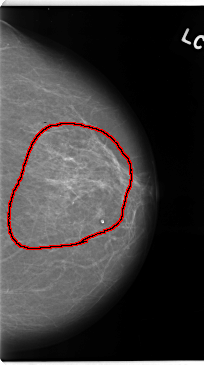

C_0138_1.RIGHT_CC

LEFT_CC LINES 4736 PIXELS_PER_LINE 2640 BITS_PER_PIXEL 12 RESOLUTION 50 OVERLAY

FILE: C_0138_1.LEFT_CC.OVERLAY

TOTAL_ABNORMALITIES 1

ABNORMALITY 1

LESION_TYPE CALCIFICATION TYPE AMORPHOUS DISTRIBUTION REGIONAL

ASSESSMENT 5

SUBTLETY 3

PATHOLOGY MALIGNANT

TOTAL_OUTLINES 1

BOUNDARY